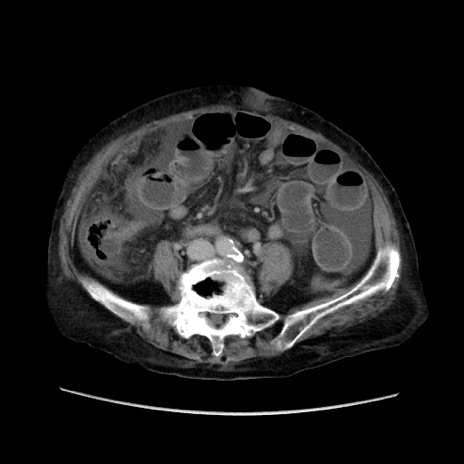

症例31(横断像)

【症例】80歳代 女性

【主訴】腹部膨満感

【現病歴】他院にて肝硬変にてフォロー中。1週間前から便秘、腹部膨満感、臍部腫瘤あり受診となる。

【既往歴】肝硬変

【身体所見】腹部膨隆あり、皮膚変化なし、疼痛なし。

【データ】WBC 4600、CRP 0.25